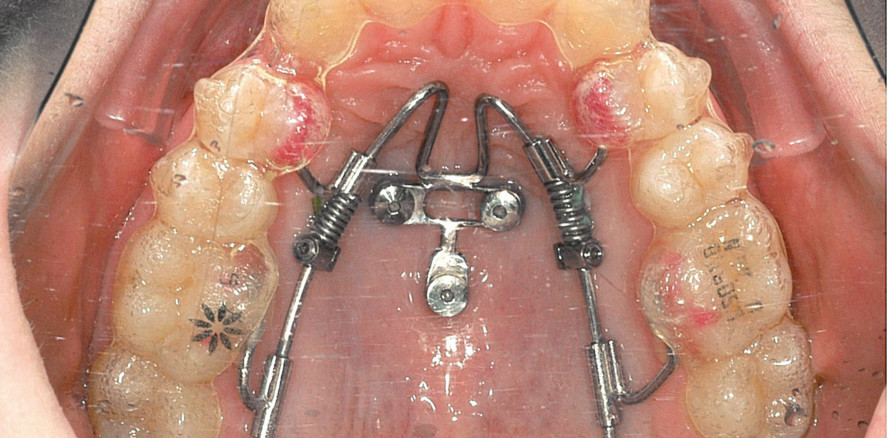

Unter den skelettalen Verankerungssystemen stehen heute die orthodontischen Miniimplantate aufgrund ihrer vielseitigen Einsatzmöglichkeiten, ihrer geringen chirurgischen Invasivität und der relativ geringen Kosten im Vordergrund.24–29 Als Insertionsregion mit einer sehr hohen Zuverlässigkeit hat sich hierbei der anteriore Gaumen erwiesen.30 Nach Insertion wird in der Regel in einem Laborprozess ein Slider hergestellt (Abb. 1).

Zum Lückenschluss und zur Mesialisierung im Oberkiefer wird heute der Mesialslider als Standardgerät eingesetzt (Fall 1), 23,31 während zur Lückenöffnung und Distalisierung der Beneslider32 verwendet werden kann (Fall 2). Als Standard werden heute zwei Miniimplantate pro Slider eingesetzt, bei besonders hohen Anforderungen, wie einer ausgeprägten Asymmetrie, kann auch eine Tripod-Verankerung mittels dreier Miniimplantate erfolgen. Als zweiter sehr wichtiger Vorteil neben der Verankerung gilt hier die körperliche Führung der Zähne, was insbesondere im Rahmen einer Alignertherapie essenziell erscheint.

Beneslider und Mesialslider können aufgrund ihrer vorgefertigten Elemente direkt intraoral oder nach Scan oder Abdruck im Labor hergestellt werden. Mittels virtueller Planung und CAD/CAM-gefertigter Insertionsschablonen können die Slider jedoch auch schon vor der Miniimplantat-Insertion hergestellt werden, sodass Miniimplantate und Slider in nur einer Sitzung eingesetzt werden können.33,34